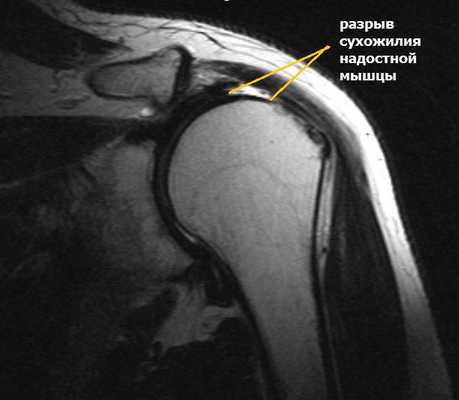

Повреждения вращательной манжеты

К повреждению сухожилий вращательной манжеты могут приводить несколько причин:

- дегенеративные изменения;

- сужение пространства между акромионом и головкой плечевой кости;

- травма;

- хроническая травматизация.

Сужение пространства между акромионом и головкой плечевой кости (импинджмент-синдром) возникает на фоне особого строения акромиального отростка или после получения травмы. Сухожилие надостной мышцы, проходящее в данном пространстве, попадает как бы в тиски и постепенно сдавливается.